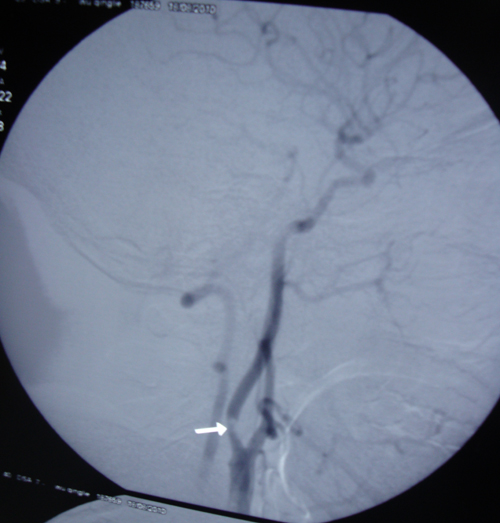

颈部血管彩超(2010-7-27):双侧颈总动脉、颅外段颈内动脉、颈外动脉内壁不光滑,内中膜增厚,右见散在混合性回声斑块,右侧较大者为 16.0mm×1.6mm,左侧较大者10.6mm×3.6mm,右侧颈内动脉可见偏低回声充填,腔内血流变细,残余管腔0.8mm,直径狭窄率为85%,血流速度增快217cm/s,右侧颈外动脉及左侧颈内动脉血流速度增快,血流速度分别为127cm/s,133cm/ s,余未见异常。

头部螺旋CT(2010-8-03):右侧颈总动脉分叉处管壁增厚,见动脉硬化软斑及钙化影,局部管腔狭窄约70%,右侧颈内动脉起始部管腔内可见直径约2.3mm低密度充盈缺损,左侧颈动脉分叉处管壁增厚,左侧颈内动脉起始部管腔狭窄50%。